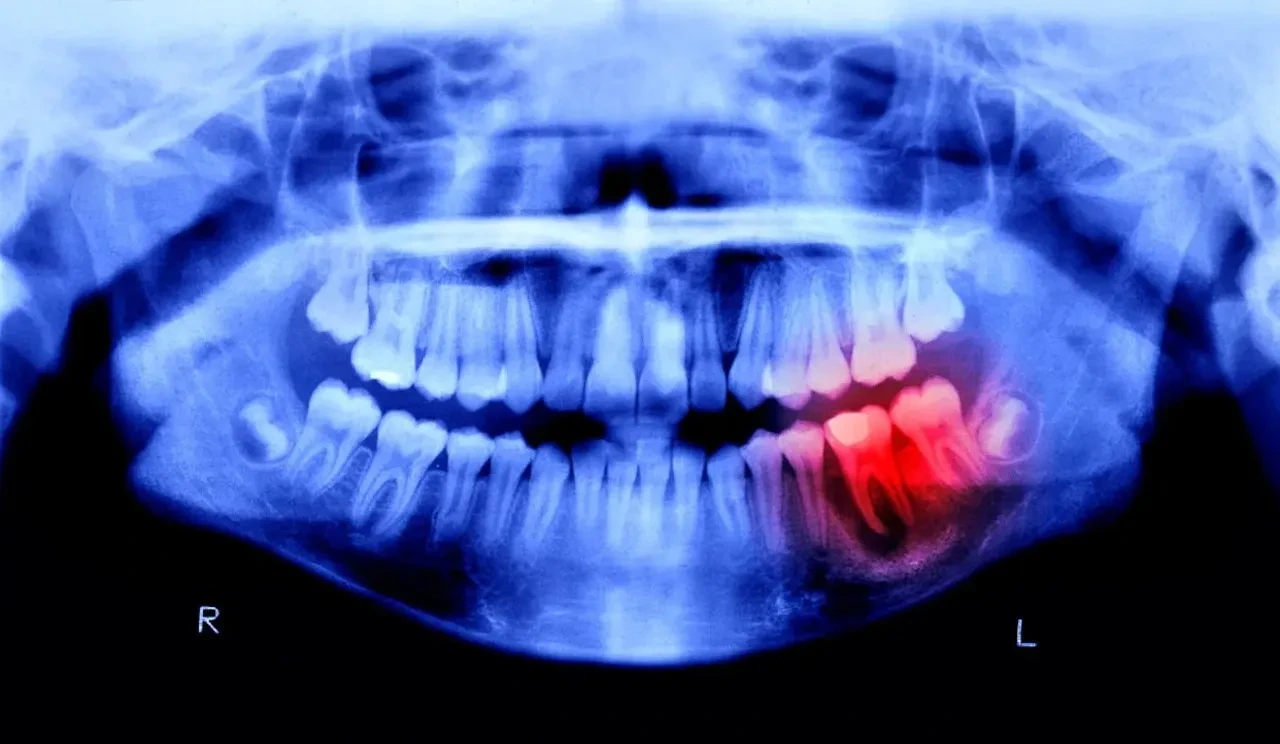

İnsan vücudundaki kemikler kırıldığında kendini onarma yeteneğine sahipken, vücudun en sert maddesi olan diş minesi maalesef aynı iyileşme mekanizmasını barındırmıyor. Japonya'nın Osaka şehrindeki Kitano Hastanesi Tıbbi Araştırma Enstitüsü'nde diş hekimliği bölüm başkanı olan Katsu Takahashi, diş kaybı veya eksikliği yaşayanlara yardımcı olmak adına kalıcı bir çözüm geliştirmeyi hedeflediklerini belirtti.

Geliştirilen teknolojinin temelinde "Uterine sensitization-associated gene-1" (USAG-1) adı verilen bir antikor yer alıyor. Geçmiş yıllarda yapılan çalışmalar, söz konusu antikorun farelerde ve gelinciklerde diş büyümesini baskıladığını ortaya koymuştu. 2021 yılında Kyoto Üniversitesi'nden bilim insanları, kanser tedavisinde sıklıkla başvurulan monoklonal antikor tekniğini kullanarak USAG-1'in etkileşimini bozmayı başardı.

Eylül ayında başlayan ve 11 ay sürmesi planlanan klinik deneyler, en az bir dişi eksik olan 30 ila 64 yaş arasındaki 30 erkek gönüllü üzerinde gerçekleştiriliyor. İlacın damar yoluyla uygulanacağı çalışmada, tedavinin güvenilirliği ve etkinliği test edilecek. Hayvan deneylerinde herhangi bir yan etkiye rastlanmaması, araştırmacılar için umut verici bir veri olarak kaydedildi.